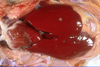

Salmonella Gallinarum

Fugle tyfus

Forstørret lever